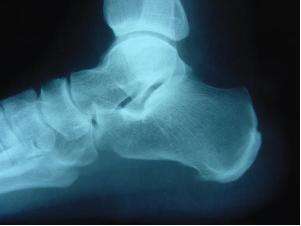

En cuanto a la patogenia de las talalgias traumáticas, los microtraumas reiterados pueden originar un proceso de periostitis con osificación de la aponeurosis en su punto de inserción. Radiográficamente esto se traduce en una imagen en forma de espina llamada espolón calcáneo (figura 1), pues recuerda el espolón del gallo, a menudo bilateral. Durante mucho tiempo se le achacó la causa del dolor a esta espina, pero se ha demostrado que su extirpación no lo hace desaparecer y que personas con espolón en ambos pies pueden tener talalgias en uno solamente. Parece ser que, tanto en este grupo como en las talalgias de crecimiento, son los traumatismos repetidos los causantes del dolor.

Figura 2. Enfermedad de Sever